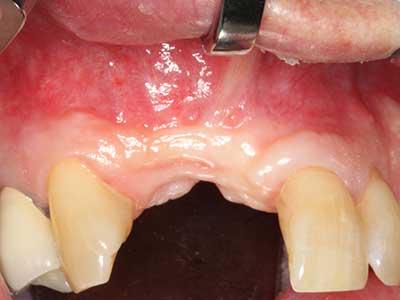

Пиезохирургията има допълнителни предимства при събиране на костни блокове. В допълнение към високата прецизност при остеотомията, описана по-горе, употребата на фините режещи накрайници значително намаляват загубата на материал. Голяма загуба на материал по време на събиране може да се очаква с дебелите накрайници, особено при употреба на борери Линдеман (Lakshmiganthan, Gokulanathan et al. 2012). Базалното разделяне, което е необходимо, особено за присадка на блок при ретромолар, е улеснено от специално създадени правоъгълни триони. В резултат на това, пиезохирургията е разглеждана като прецизна, улеснена и безопасна процедура за събиране на костни блокове в ретромоларното пространство (Happe 2007) (Фиг. 1-12).

Костната тъкан е не само минерализирана структура, тя съдържа и съществено количество колагенови влакна. Това означава, че тя има не само добра компресивна сила, но и известна степен на гъвкавост, която може да се възприеме като предимство при извършване на костна аугментация. В класическата процедура по разширяване чрез костно разделяне, атрофиралият алвеоларен гребен е разделен надлъжно и внимателно разширен след достигане на подходящата остеотомна дълбочина (Фиг. 13-16), в идеалния случай без допълнително отстраняване на периостеума (Brugnami, Caiazzo et al. 2014, Stricker, Fleiner et al. 2014). Системите с винт и пластини с увеличаване на разстоянието при разширяване са доказали ефективността си при разделяне на двете костни ламели, оставайки под прага на фрактурите. В общи линии, оставащата ширина на костта от поне 3–4 mm е задължителна (Chiapasco, Zaniboni et al. 2006), за да се гарантира добра гъвкавост и достатъчно костно покритие за бъдещото поставяне на импланти. Ако е необходимо, вертикалната остеотомия на едната или двете страни може да подобри гъвкавостта. Комбинацията с допълнителни техники за аугментация, особено в букалната страна, е описана като алтернатива на класическата техника.